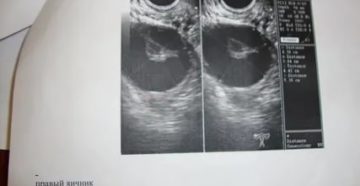

Шоколадная киста яичника — как лечить, причины и симптомы болезни Под названием эндометриодная (шоколадная) киста…